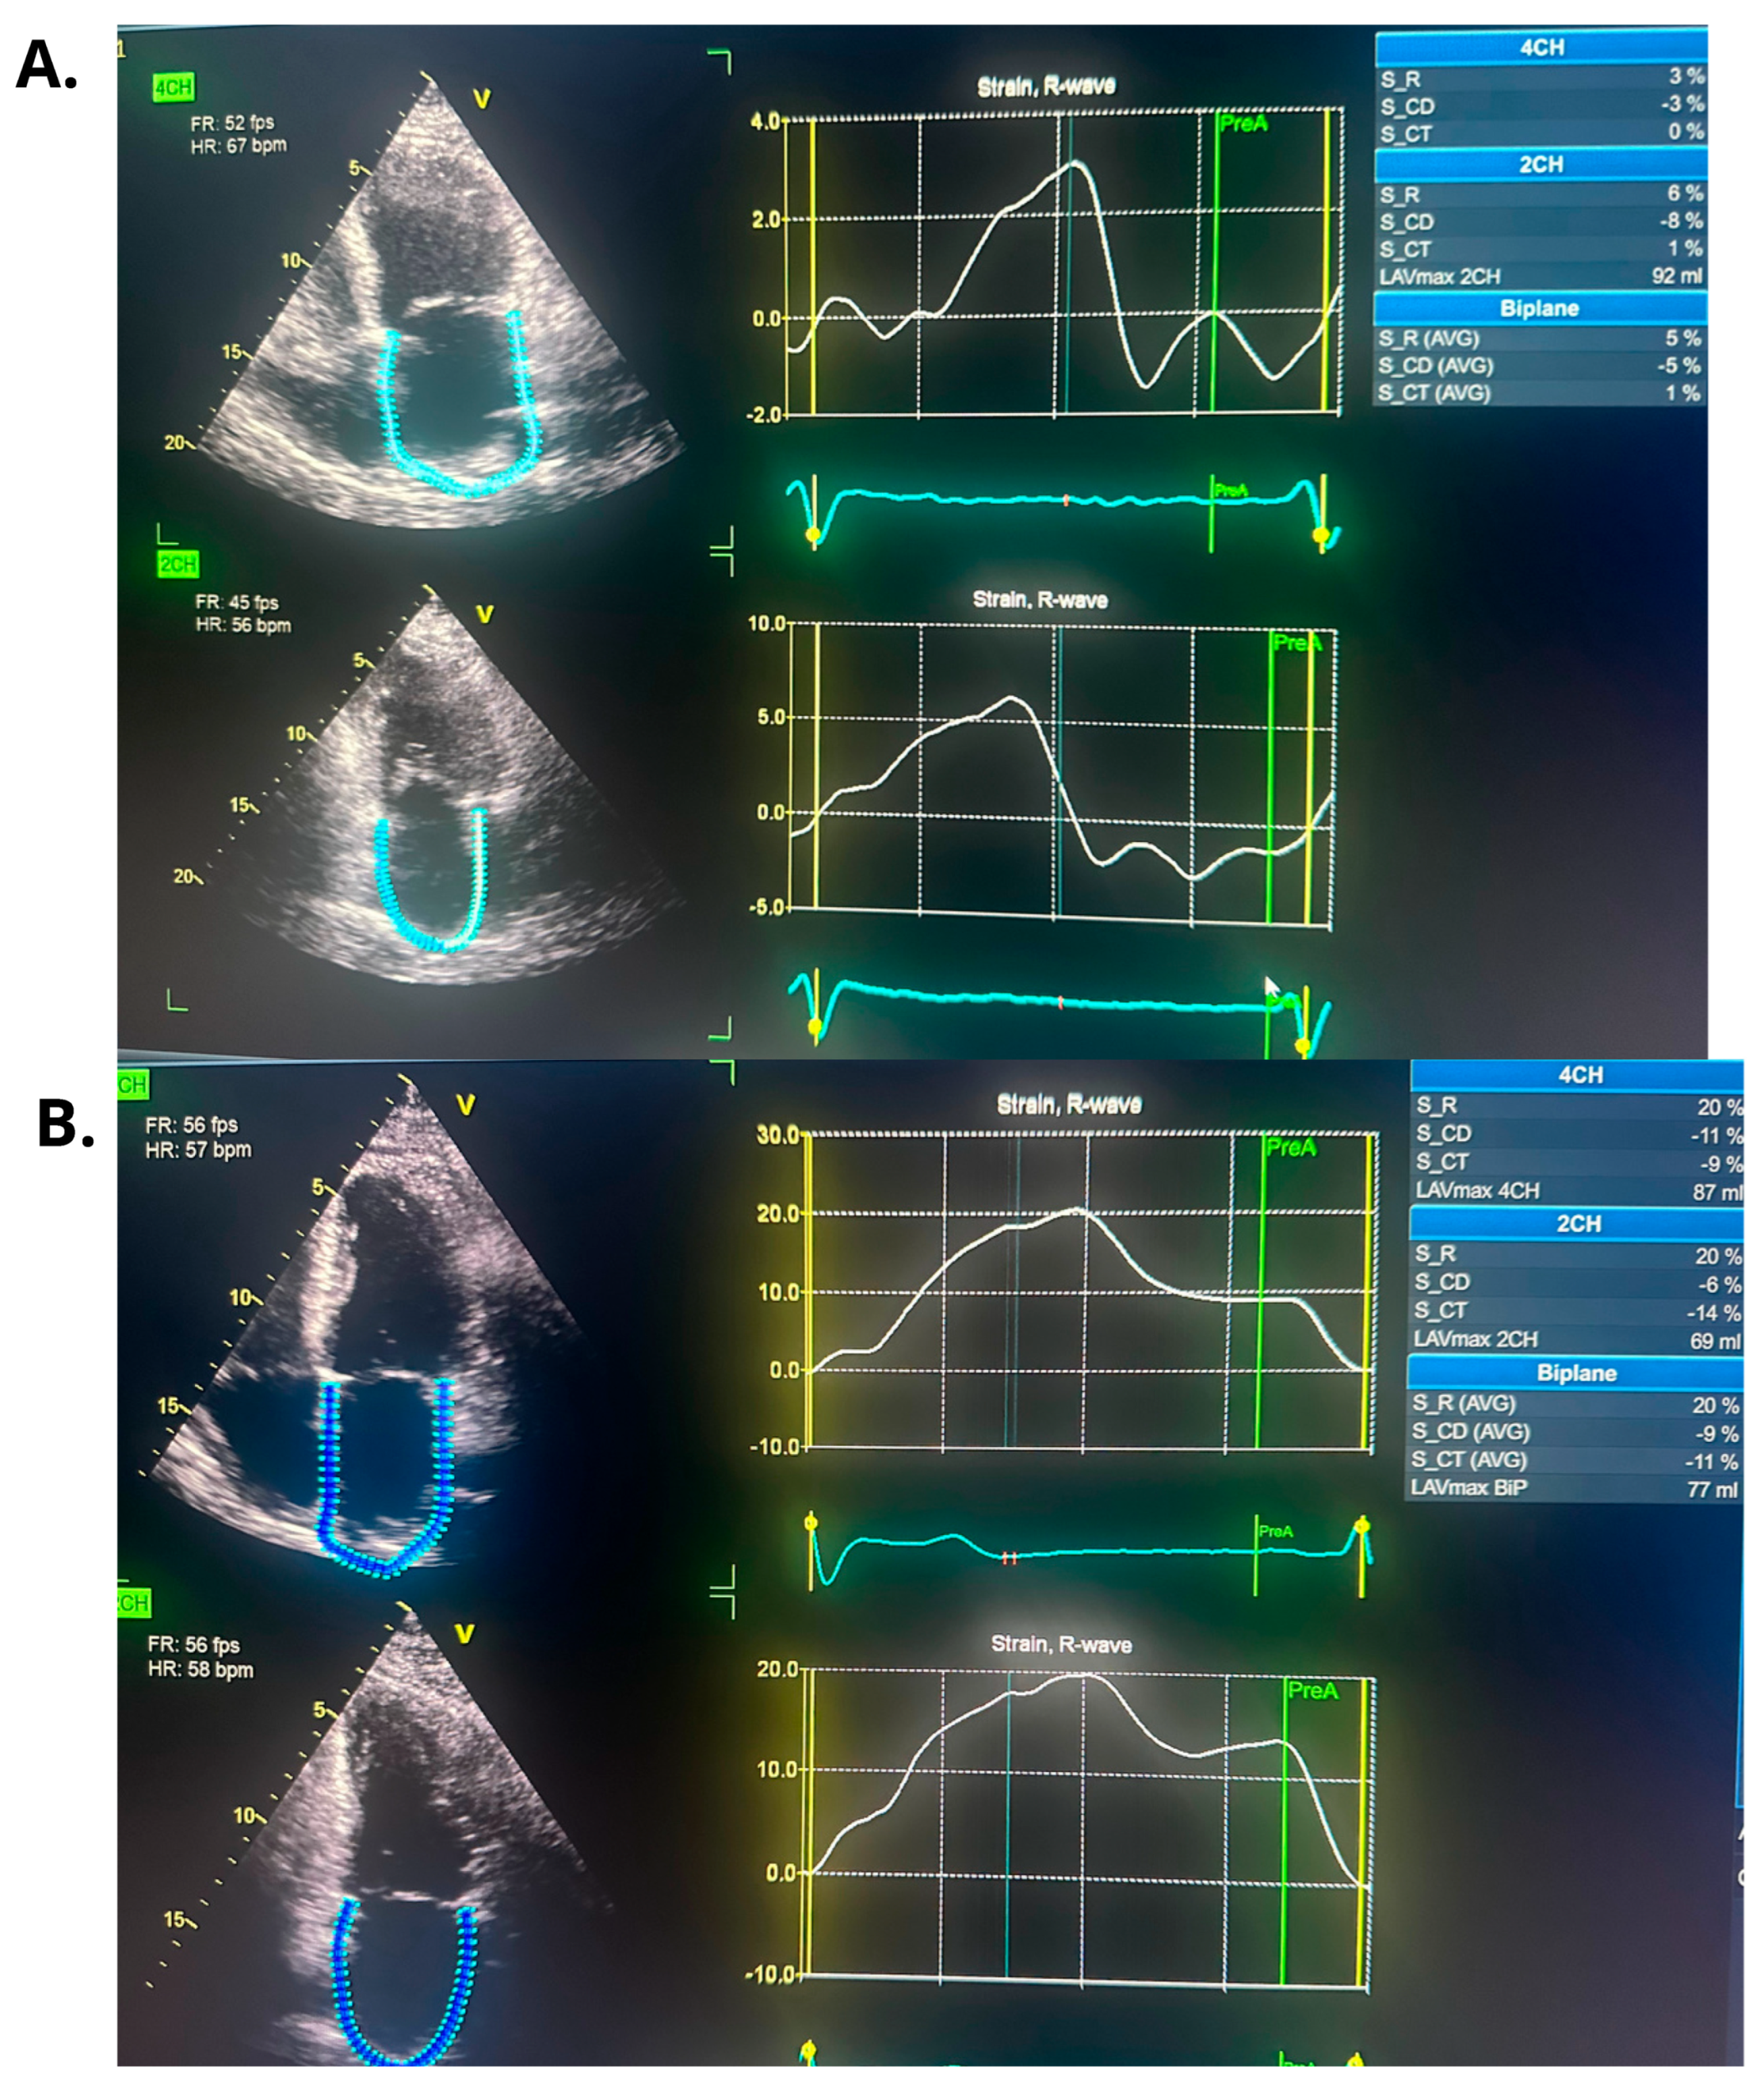

Repeated TTE demonstrated a slight improvement in left ventricular systolic function, with an LVEF of 25%. (Figure 3 and Figure 4).

Following the ablation procedure, chronic amiodarone therapy was discontinued. The patient was subsequently scheduled for follow-up visits approximately 2 months and 14 months after the intervention. Since the ablation, the patient remained in very good general condition, with no documented recurrences of arrhythmia, either symptomatically or on 24 h Holter ECG monitoring. There were no hospitalizations for arrhythmia-related events during this period. At the 14-month follow-up, TTE was performed and complete normalization of left ventricular systolic function was observed, with an LVEF of 55% (Figure 3 and Figure 4). Additionally, a reduction in the dimensions of both atria, the right and left ventricles, was noted. The previously elevated natriuretic peptide levels had also regressed significantly. Importantly, the patient’s functional status and quality of life improved markedly, as assessed by the ASTA questionnaire, with a score reduction from 24 points before the procedure to 0 points after ablation. General and echocardiographic parameters before and after ablation are presented in Table 2, Table 3 and Table 4 respectively.

In our patient, catheter ablation resulted in a marked improvement of left atrial mechanical function, as assessed by LA strain. While such functional recovery may not be achievable in every patient with persistent atrial fibrillation and impaired left atrial strain [16], it could potentially have meaningful implications for long-term outcomes, including thromboembolic events and stroke, as suggested by available literature [17,18].

Figure 4. The figure illustrates changes in left atrial strain parameters observed before and following catheter ablation. (A). Left atrial strain parameters before ablation (during ongoing atrial fibrillation). (B). Left atrial strain parameters after ablation in follow-up time (during sinus rhythm).